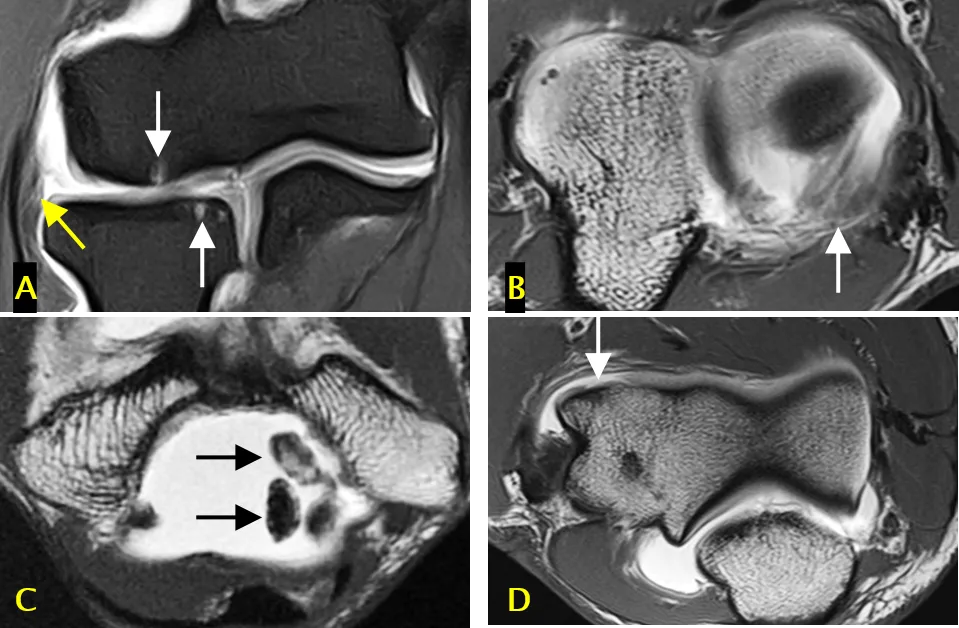

标注 A(冠状面脂肪抑制 T1 加权直接 MR 关节造影像)、B-D(轴面 T1 加权直接 MR 关节造影像):

• A 图:骨软骨损伤(白色箭头)和外侧尺侧副韧带全层撕裂(黄色箭头)

• B 图:后外侧滑膜皱襞(箭头)

• C 图:关节内游离体(箭头)

• D 图:全层软骨缺损(箭头)